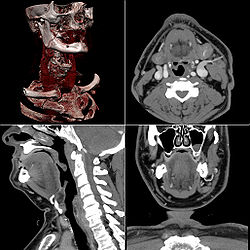

Jod kao teški element je pogodan za radiloško snimanje, jer radi sjene (kontrast) na snimkama kod računalne tomografije i angiografije. Angiološki pregledi predstavljaju kontrastne invazivne dijagnostičke radiološke metode pregleda srca i krvnih žila. Indikacije za te preglede predstavljaju bolesti krvožilnog sustava, centralnog živčanog sustava, sredoprsja i pluća, trbušnih organa i urogenitalnih organa. Oni su postali nezamjenjive u dijagnostici kongenitalnih vaskularnih malformacija, ateromatoze, tromboze i embolije te u dijagnostici tumora i oboljenja parenhimnih organa. Može se reći da je arteriografija znatno pridonijela napretku medicine uopće. Kontraindikacije za tu vrstu dijagnostike jesu opće loše stanje pacijenta, produženo vrijeme krvarenja, smanjen broj trombocita, kao i dokazana alergija na jod, koji je sastavni dio kontrastnog sredstva.